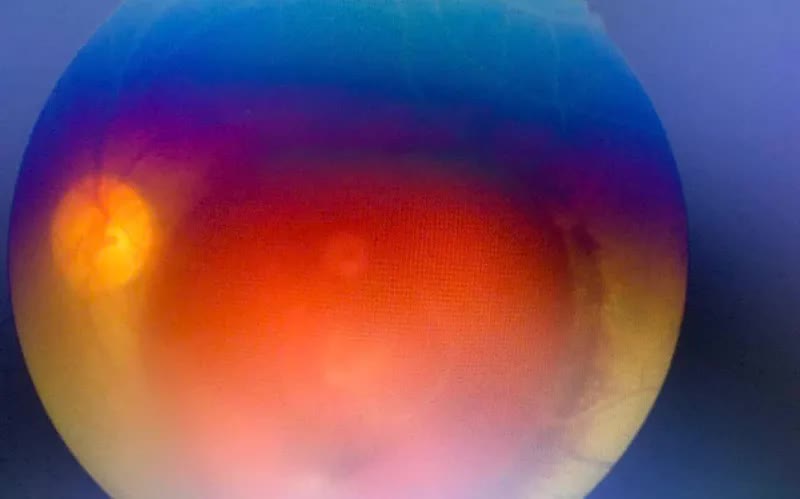

Kết quả thăm khám cho thấy thị lực mắt phải 10/10, mắt trái thị lực giảm trầm trọng, chỉ còn có thể đếm ngón tay khoảng cách 1,5 m (ĐNT 1,5 m). Kết quả soi đáy mắt và chụp hình màu đáy mắt trái là hình ảnh xuất huyết trước võng mạc và sau màng Hyaloid.

Các bác sĩ đã tiến hành hội chẩn các giáo sư đầu ngành Bệnh viện Mắt Trung ương, tiên lượng điều trị phức tạp, khả năng phục hồi thị lực khó khăn, có thể để lại ám điểm vĩnh viễn do tổn thương hoàng điểm không hồi phục.